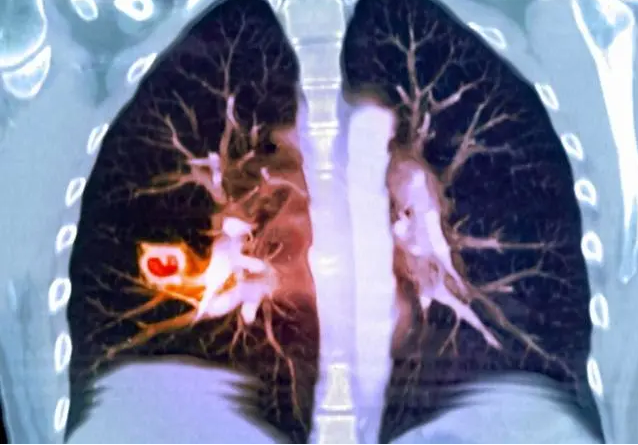

肺结节是肺部直径小于或等于3厘米的类圆形或不规则病变。因为是肺部病变,正常人肯定不会患。通过对肺结节的病理学研究发现,肺结节的病理表现为淋巴细胞、单核巨噬细胞和非干酪样坏死性上皮细胞肉芽肿的形成。它的出现与遗传、职业、环境、感染等诸多因素有关。例如长期接触石棉、氯乙烯等。在工作中,这些物质吸入肺部后会产生免疫反应,肺实质因炎症反应的组织和包装而形成结节,或因结核病或真菌感染而诱导结节的形成。

可以说,大多数肺结节并不严重,许多患者没有症状。然而,在临床上,肺结节有一定的可能性是肺癌或发展为肺癌,因此它们不能被忽视。根据影像学表现的密度,肺结节可分为三类:实性结节、部分实性结节和磨玻璃结节。根据直径的不同,这三种类型的结节有不同的严重程度和治疗方法。